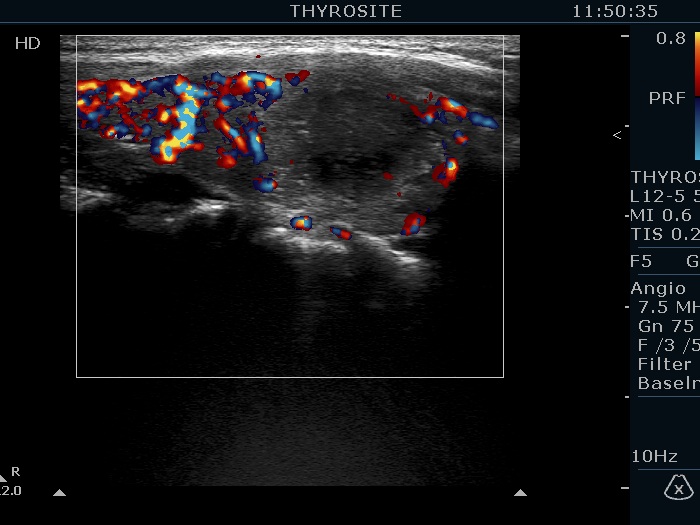

Right lobe, longitudinal scan

Right lobe, longitudinal view, color Doppler mode. The lesion is avascular.